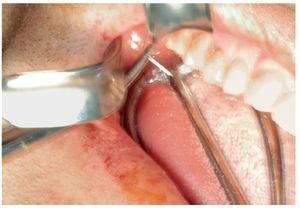

Un paciente de 35 años de edad acudió a la consulta de su odontólogo de cabecera por un cuadro de dolor agudo en el lado derecho de la mandíbula. La punta de la aguja se rompió durante la anestesia de conducción del nervio dentario inferior. No fue posible localizarla desde la cavidad oral. El paciente fue remitido para su diagnóstico y tratamiento urgente a la Clínica de Cirugía Maxilofacial de la Clínica Universitaria de Zúrich. Una ortopantomografía obtenida por el odontólogo de cabecera evidenciaba claramente la punta rota en proyección sobre la tuberosidad maxilar derecha (fig. 1). A su llegada a la clínica el paciente estaba asintomático. En la exploración clínica no se logró localizar con precisión la aguja. Se practicó una tomografía computarizada para una evaluación exacta. En la TC se observó la aguja rota en la zona del tejido adiposo y la cara inferior del músculo masetero directamente en medial del arco cigomático y en la parte anterior de la rama ascendente de la mandíbula (fig. 2).

Figura 2. La tomografía computarizada craneal muestra una imagen radioopaca de densidad metálica de aproximadamente 20 mm de largo en la zona del músculo masetero derecho.